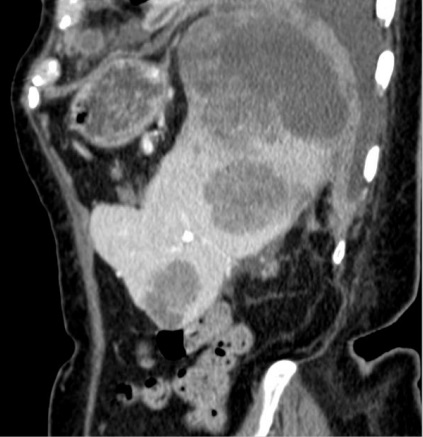

Même cas en coupe sagital a

volumineuse et sa contenue être en vue très net |

Aspect lesionelle des

arterielles ,en coupe coronal . |